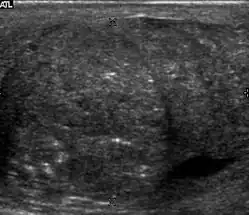

Seminoma is the most common tumor type in cryptorchid testes. The risk of developing a seminoma is increased in patients with cryptorchidism, even after orchiopexy. There is an increased incidence of malignancy developing in the contralateral testis too, hence sonography is sometimes used to screen for an occult tumor in the remaining testis. On US images, seminomas are generally uniformly hypoechoic, larger tumors may be more heterogeneous [Fig. 3]. Seminomas are usually confined by the tunica albuginea and rarely extend to peritesticular structures. Lymphatic spread to retroperitoneal lymph nodes and hematogenous metastases to lung, brain, or both are evident in about 25% of patients at the time of presentation.

Patients with testicular lymphoma are usually old aged around 60 years of age, present with painless testicular enlargement and less commonly with other systemic symptoms such as weight loss, anorexia, fever and weakness. Bilateral testicle involvements are common and occur in 8.5% to 18% of cases. At sonography, most lymphomas are homogeneous and diffusely replace the testis [Fig. 7]. However focal hypoechoic lesions can occur, hemorrhage and necrosis are rare. At times, the sonographic appearance of lymphoma is indistinguishable from that of the germ cell tumors [Fig. 8], then the patient's age at presentation, symptoms, and medical history, as well as multiplicity and bilaterality of the lesions, are all important factors in making the appropriate diagnosis.